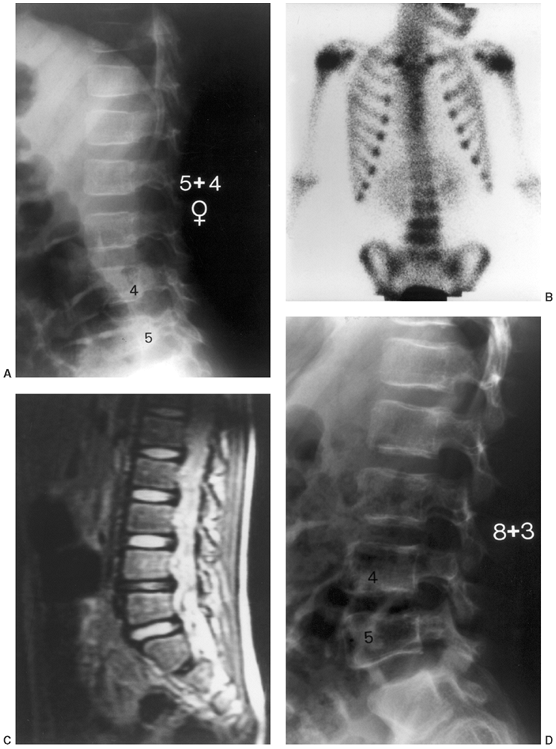

![]() |

Figure 13.3 A:

A 2-month-old infant presents following 3 days of increasing irritability, fever, and pseudoparalysis of the right leg. Anteroposterior pelvis radiograph demonstrates widening of the right hip joint space. B: The patient was rushed to the operating room, where the right hip was aspirated and an arthrogram was performed to document intraarticular position of the needle. Cell count of the hip joint aspirate was 65,000 per mL; open joint irrigation and debridement of septic arthritis was performed. C: Two years following open surgical irrigation and drainage, the patient is asymptomatic but on performing radiography is found to have mild hip dysplasia on the right with acetabular index of 25 degrees compared to 22 degrees on the left, 50% femoral head coverage on the right compared to 70% coverage on the left, and widening of the right femoral neck. D: Four years following irrigation and debridement, the right hip dysplasia has improved, with the right acetabular index now measuring 21 degrees and with a femoral head coverage of 70%. Mild coxa magna and femoral neck widening persists. |